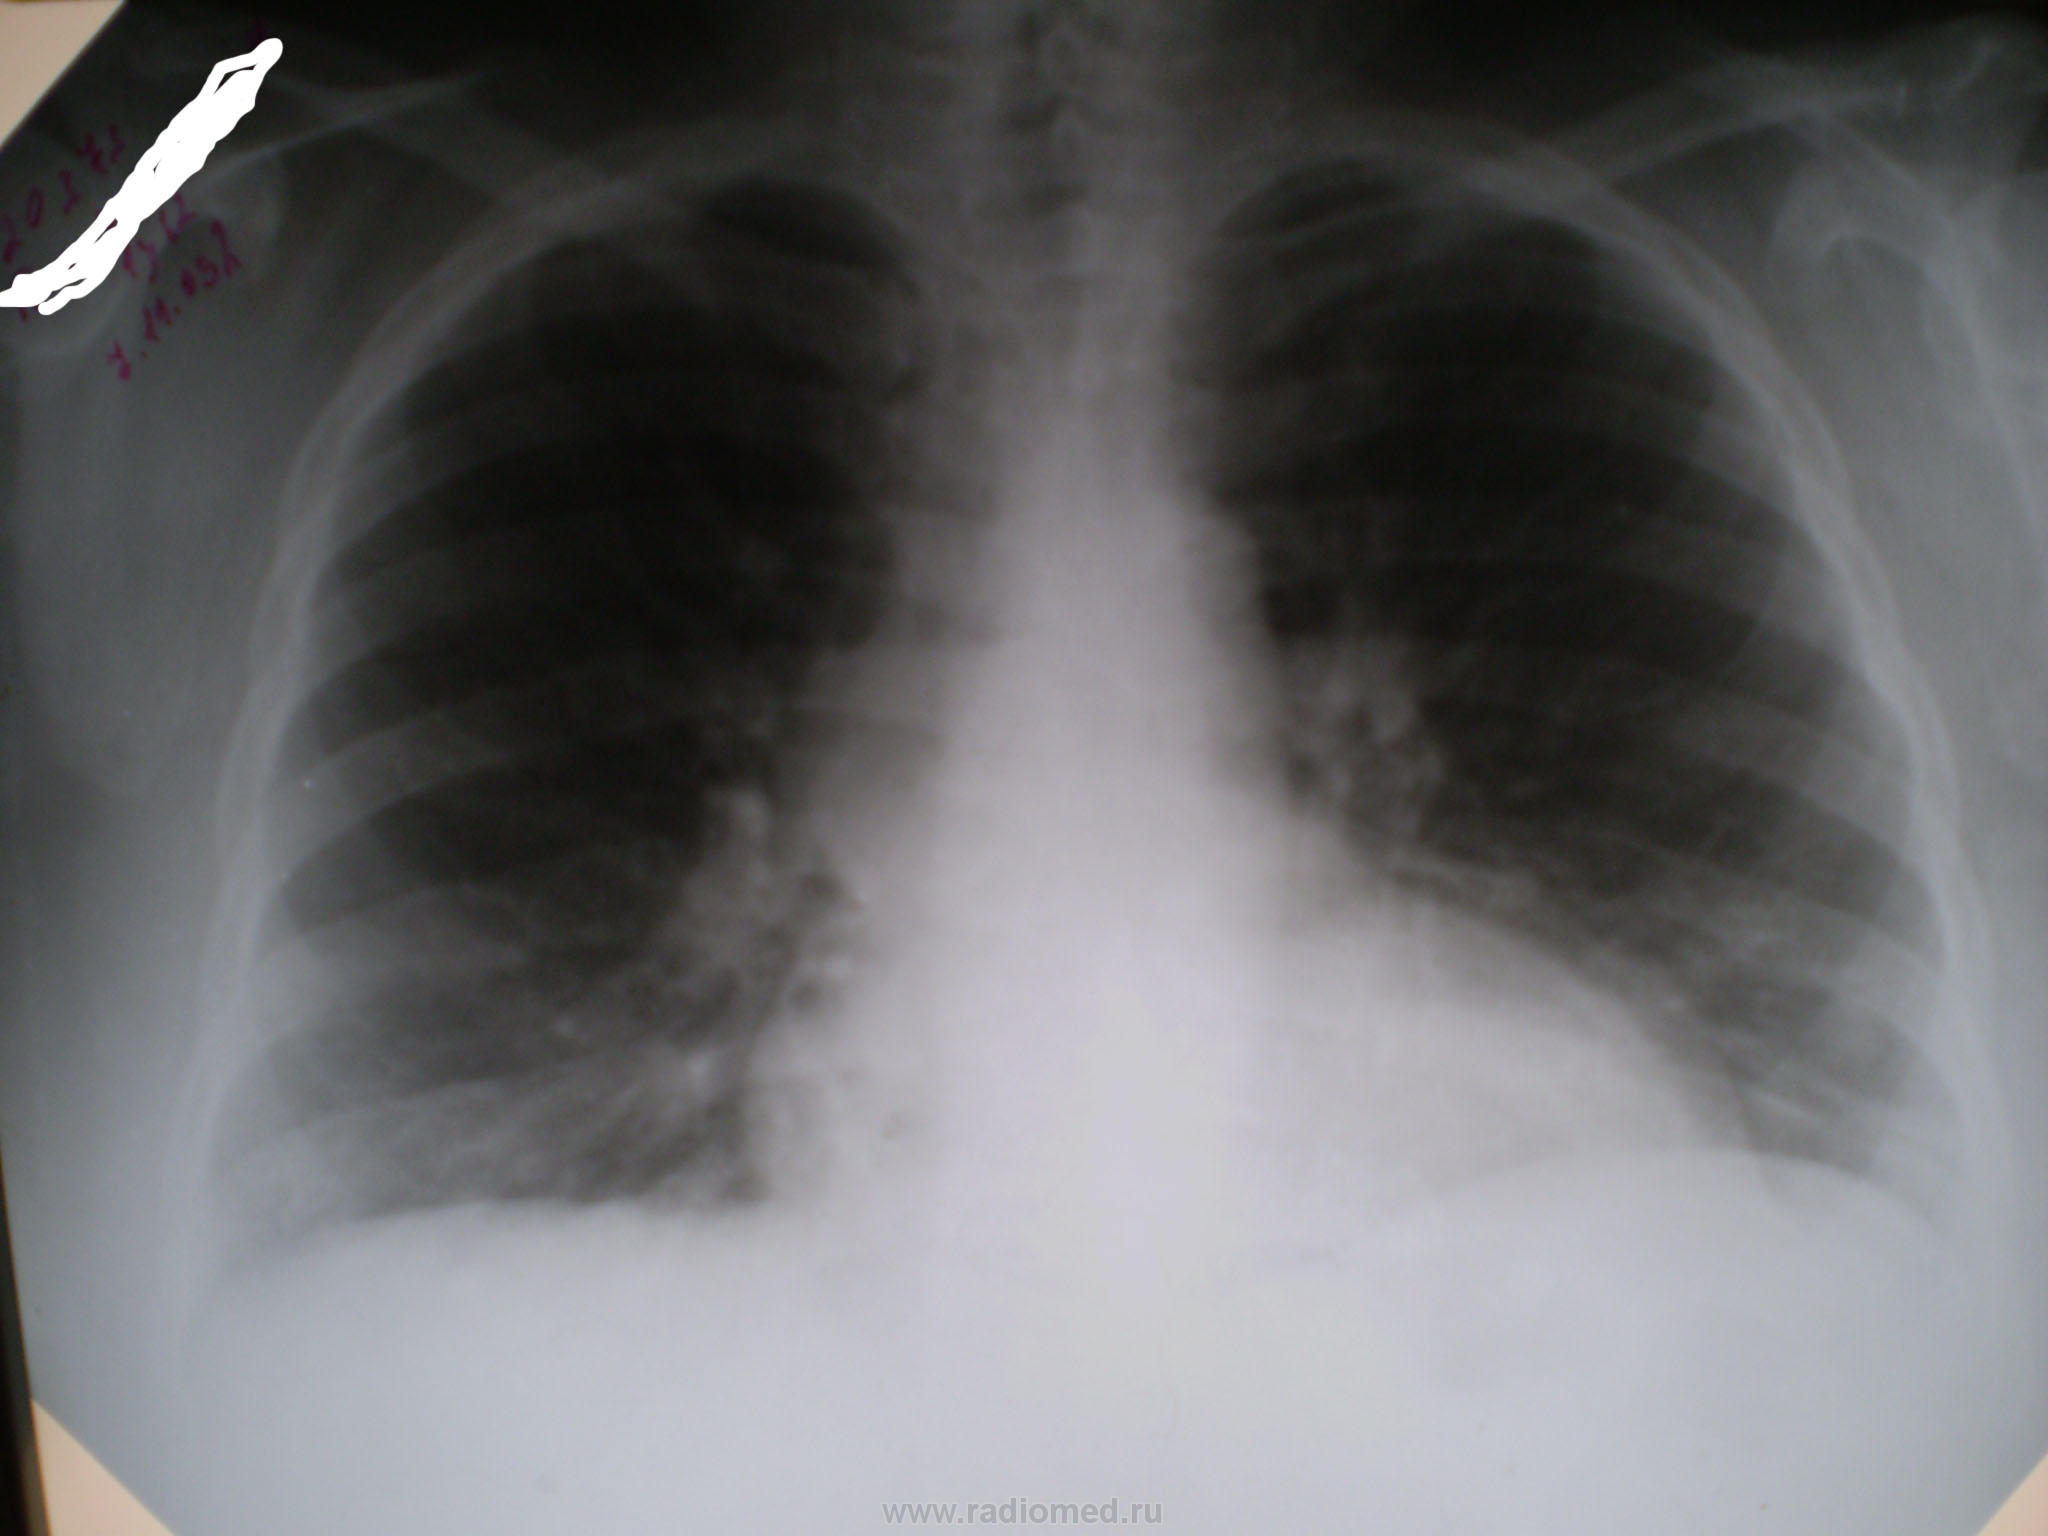

Больная Б. 1962г.р., поступила в ЦРБ 7.11.2009г. с температурой 40, всеми признаками ОРЗ в самый грипозный период. Сделали снимок. На второй день ей лучше, t-37,5. Вечером 10.11.12 - t-38,0, резкая слабость, недомогание, одышка. Сатурация - 87%. В крови - L-7, РОЭ- 28. Утром 11.11.09 сделали повторный снимок, перевели в реанимацию, откуда вечером в морг. Какие мнения?

Как вариант - "свиной грипп", только у него, вроде бы, "светлых" прмежутков не бывает. Тогда вариант 2: у женщины с кардиальными проблемами обычный грипп, затем лучше, затем кардиальные осложнения (миокардит и все такое), декомпенсация, отек легких и все.

И этот вариант подтверждён паталогоанатомом. У всех четверых, умерших в то время в нашей больнице от "свинного гриппа" был светлый промежуток. Кстати, кафедра судебной медицины Черновицкого мединститута патоморфологически доказывала, что тогда была не вирусная пневмония, а респираторный дистрес-синдром взрослых в ответ на сильную вирусную интоксикацию.

Гистологически, патоморфологически - все соответствует синдрому гиалиновых мембран (оно-же РДС взрослых, оно-же шоковое лёгкое). А разработок НАСА никто здесь и не использовал.

По первому снимку: есть в нижней зоне три кругляшки, которые накладываются на ребра. В дальнейшем отрицательная динамика, причем справа с худшим вариантом.

Было тоже несколько подобных случаев несколько лет назад во время эпидемии гриппа, очень быстрое ухудшение клинически и рентгенологически до реанимации, неэффективность лечения и ИВЛ, летальный исход, молодой и средний возраст